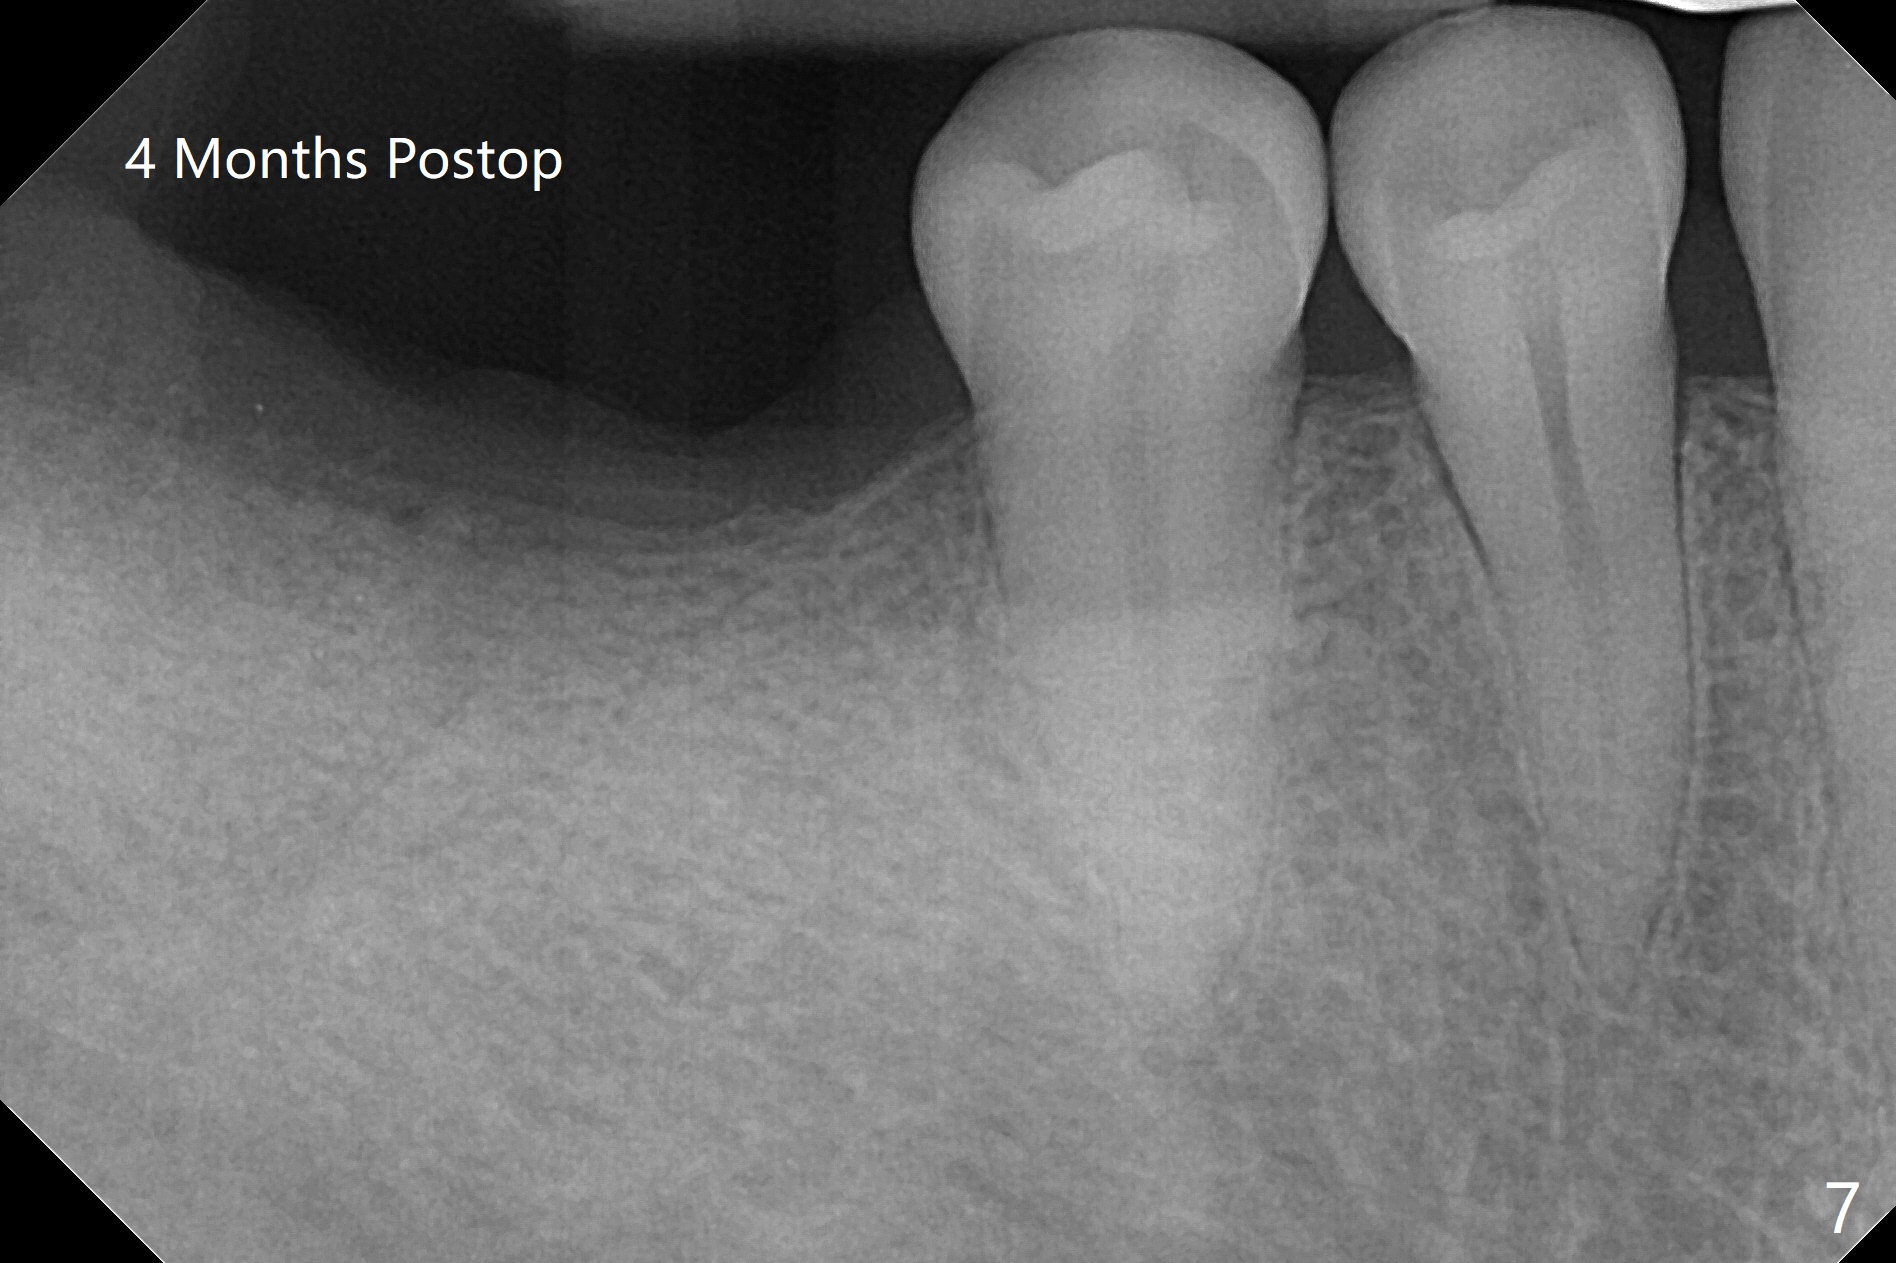

Since the tooth #31 is mesially shifted and tilted with mobility, it would not be a good distal anchor tooth for #30 implant placement with a surgical guide. It is extracted when an implant is placed at #3 so that autogenous bone harvested from the osteotomy at #3 will be mixed with allograft (Vanilla) and alloplast (Osteogen) for #31 socket preservation (Fig.3 M). After Osteogen plug and 6-month membrane are placed over the mixed graft, the socket is approximated with 5-0 PGA (Fig.1,2). The 6-month membrane appears to be retained 5 days postop (Fig.4). The socket reduces substantially nearly 1 month postop (Fig.5,6). The small 2nd molar socket (as compared to the 1st molar one) heals quick. PGA suture should be used more often (for more cases and repeat multiple times for secure closure). The bone density in the graft area increases 4 months postop (Fig.7). The graft remains in site nearly 11 months postop (Fig.8). The ridge #30 will be split with guide. In fact there is not much problem when the osteotomy moves lingual.